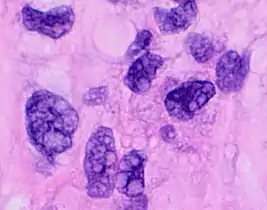

Pleomorphic when having different sizes and shapes. This often correlates with an increased nucleus to cytoplasm ratio. These features generally indicate malignancy.